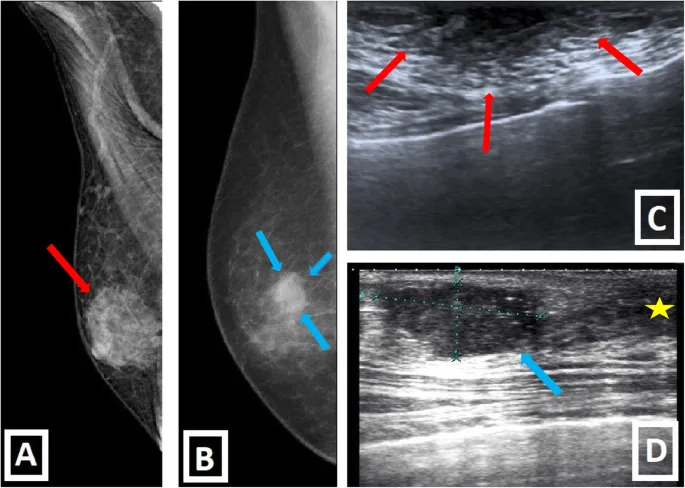

- Mammography: Eccentric, spiculated mass; microcalcifications less common.

- Ultrasound: Hypoechoic, irregular mass; posterior acoustic shadowing.

- Malignancy: Spiculated, eccentric mass; suspicious calcs.

- Malignancy: Irregular, anti-parallel, spiculated, shadowing, vascular.

⭐ On mammography, gynecomastia typically presents as a retroareolar density, whereas male breast cancer is often eccentric to the nipple and may have suspicious calcifications or spiculation.